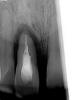

drusmanov Опубликовано 17 мая, 2011 Поделиться Опубликовано 17 мая, 2011 а в этом случае? у кого какие мысли? Ссылка на комментарий

Bier Опубликовано 17 мая, 2011 Поделиться Опубликовано 17 мая, 2011 я бы удалил, выскреб грануляции и добился заживления, дальше бы смотрел. Ссылка на комментарий

Astronaft Опубликовано 17 мая, 2011 Поделиться Опубликовано 17 мая, 2011 (изменено) а в этом случае? у кого какие мысли?A что за история у зуба?После удаления заживет быстро, но немедленно десне поддержка нужна. Изменено 17 мая, 2011 пользователем Astronaft Ссылка на комментарий

drusmanov Опубликовано 17 мая, 2011 Поделиться Опубликовано 17 мая, 2011 A что за история у зуба?После удаления заживет быстро, но немедленно десне поддержка нужна. пациент обратился 10.05.11.. Подвижность супермега 1000 степени. Удалил, кюретаж. Изготовили бабочку. Думаю подожду 3-4 недели, десна пусть созреет. Ну для кости нужно ждать 2-3 мес .. Ссылка на комментарий

Bier Опубликовано 17 мая, 2011 Поделиться Опубликовано 17 мая, 2011 пациент обратился 10.05.11.. Подвижность супермега 1000 степени. Удалил, кюретаж. Изготовили бабочку. Думаю подожду 3-4 недели, десна пусть созреет. Ну для кости нужно ждать 2-3 мес ..бабочка сожрет там всю десну. Ссылка на комментарий